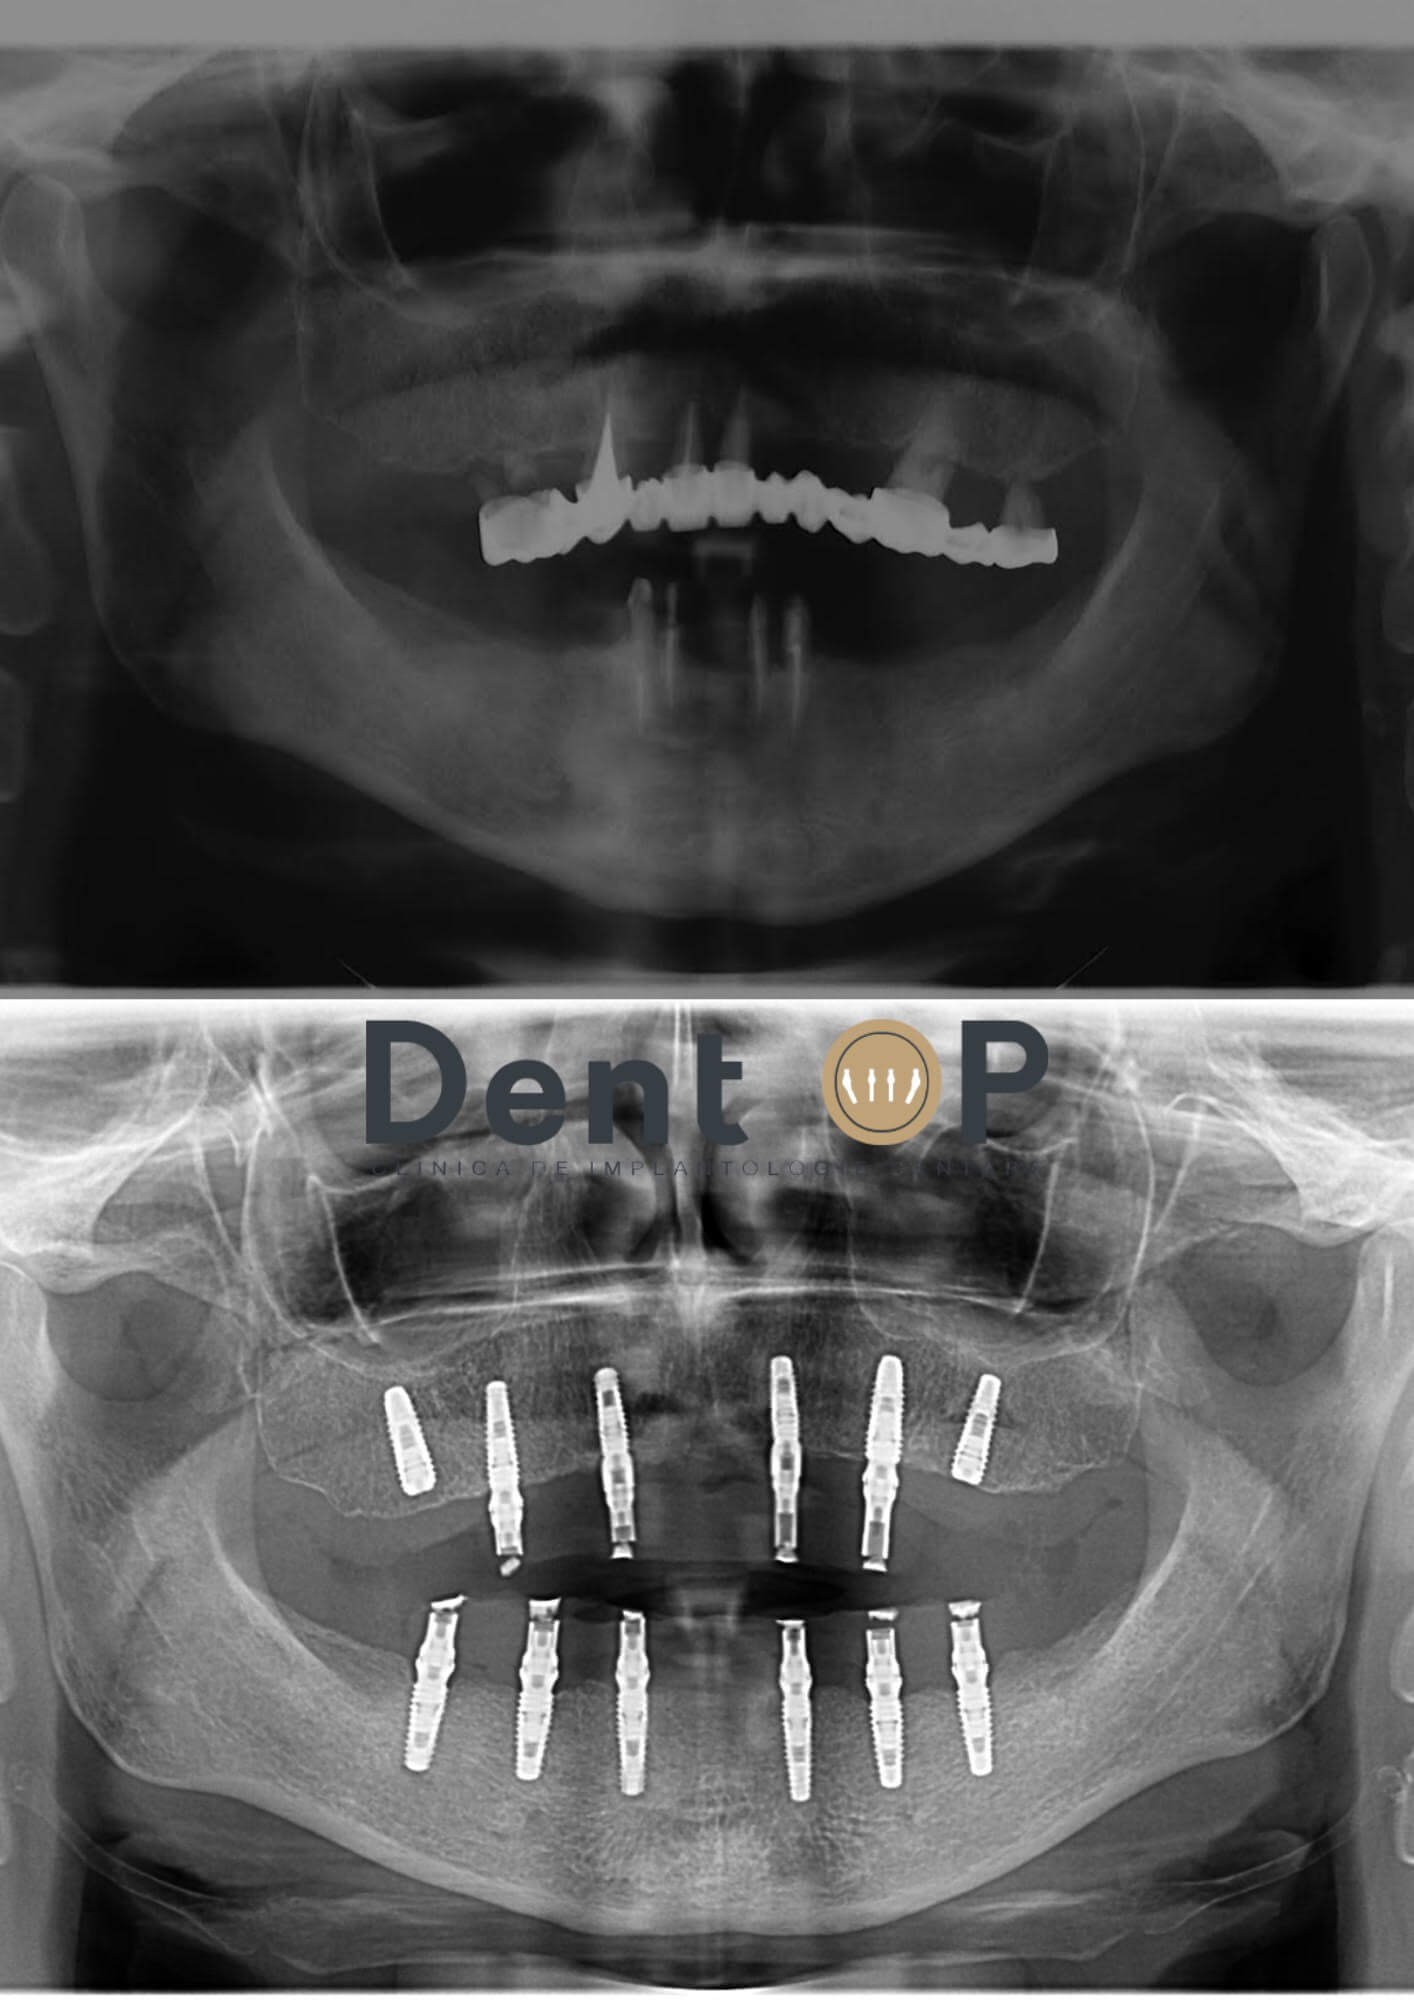

Doamna M. a ales procedura ,,Dantură Fixă în 24h pe implanturi dentare” la recomandarea Dr Cazacu Corrado – Medic Specialist Chirurgie Dento-Alveolară. După o analiză amănunțită a radiografiei si computerului tomograf al pacientei, Dr Cazacu Corrado a decis inserarea a 12 implanturi dentare dintre care 6 la maxilar și 6 la mandibulă.

In radiografia de mai jos vom putea observa cum arata radiografia doamnei M. înainte și după inserarea implanturilor.